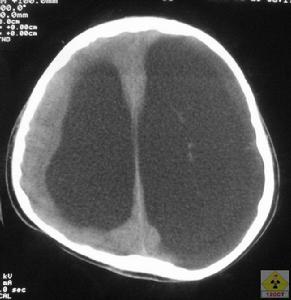

4、頭顱CT或MRI可以顯示雙側腦室對稱性擴大第三腦室及第四腦室也擴大腦萎縮連續顱內壓監護可發現患者熟睡後的眼動期出現顱內壓升高現象據此可與腦萎縮引起的老年性痴呆相鑑別腰椎穿刺示腦脊液壓力正常,CSF檢查正常

1.影像學檢查頭顱CT檢查是正常顱壓腦積水檢查重要手段,它可確定腦室擴大和皮質萎縮的程度及引起腦積水的病因,同時,也是觀察術後分流效果及併發症的手段。典型的CT掃描表現為腦室擴大而皮質萎縮不明顯。MRI影像可從矢、冠、水平全方位觀察較小的顱內病變並優於CT,同時通過MRI可觀察腦脊液的動力學變化,對腦積水進行評價。腦室周圍T1加權像低信號改變可表明腦積水呈進展趨勢。

頭顱CT掃描3、分流失敗分析:對正常顱壓腦積水選擇合適壓力的分流管至關重要,只有分流後使腦壓儘可能降低才能達到腦室縮小、症狀改善的效果。但腦壓下降過度則會引起術後一些合併症: